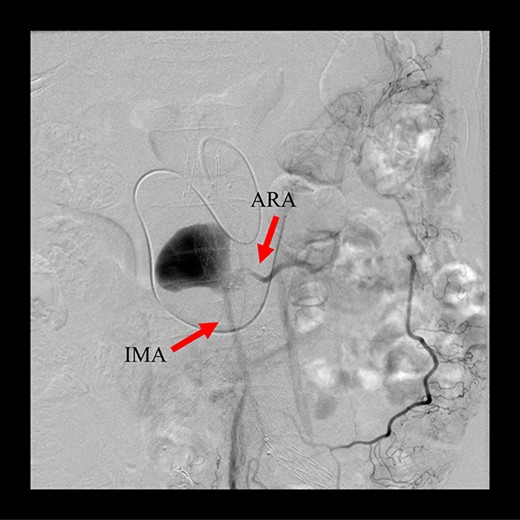

Angiography for decision-making revealed a type II endoleak from the IMA to the AAA, but no other visible endoleak (Fig. 2). Based on these findings, we planned additional EVAR for left CIAA, which was thought to have enlarged in natural course, and IMA embolization for the type II endoleak associated with sac enlargement. A staged strategy was devised. IMA embolization was planned several days after EVAR. Sac angiography from the IMA via Riolan’s arcade showed a flow-through endoleak to the ARA as a drainage artery (Fig. 3). Based on this finding, we embolized the ARA and the IMA with coils via Riolan’s arcade (Fig. 4). Selection and embolization of the drainage artery were technically feasible because of the flow from the IMA to the ARA. No deterioration of renal function due to ARA embolization was observed. One year after treatment, a CT scan demonstrated that the sac shrank to 42 mm with no evidence of a continuing endoleak (Fig. 5).

Coil embolization of the IMA and ARA was performed successfully via Riolan’s arcade.